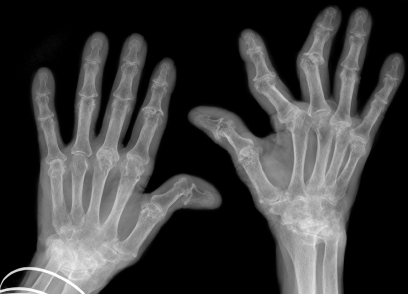

Представляет собой хроническое воспалительное заболевание суставов, характеризующееся длительным течением. Причиной его возникновения является нарушение иммунитета. В основном болеют люди в возрасте 20-50 лет (женщины чаще, чем мужчины).

Усталость, утренняя скованность (длительностью более 1 часа), широкое распространение боли в мышцах, потеря аппетита, слабость, деформация суставов (в основном в руках).